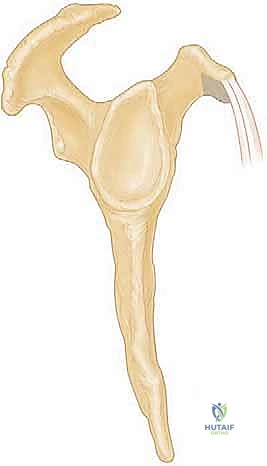

4. الناتئ الغرابي (Coracoid Process)

هو بروز عظمي يشبه منقار الغراب يمتد من لوح الكتف إلى الأمام. يمر وتر العضلة تحت الكتف أسفل هذا البروز مباشرة. في بعض الأشخاص، تكون المسافة بين الناتئ الغرابي والوتر ضيقة جداً، مما يؤدي إلى احتكاك مستمر (انحشار) يسبب تآكل الوتر وتمزقه بمرور الوقت.

3. الخطوة الأولى: تصغير الناتئ الغرابي (Coracoplasty)

إذا كان هناك ضيق في المسافة تحت الغرابية يسبب انحشاراً، يجب معالجة السبب الجذري قبل إصلاح الوتر، وإلا سيتعرض الوتر للتمزق مرة أخرى.

* يستخدم الدكتور هطيف أداة تنعيم دقيقة (Burr) لبرد وإزالة جزء من العظم من أسفل وجانب الناتئ الغرابي.

* يتم توسيع المسافة لتصبح حوالي 7 ملم على الأقل، مما يخلق نفقاً آمناً وواسعاً يتحرك فيه وتر العضلة تحت الكتف بحرية دون أي احتكاك.